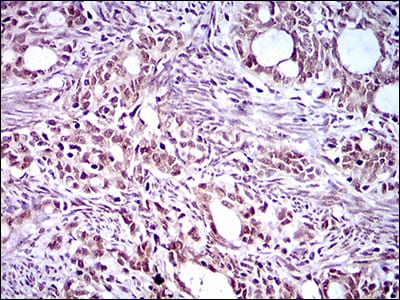

分类: 科研抗体货号: 30507别名: FLK2; STK1; CD135; FLK-2应用: IHC反应种属: Human